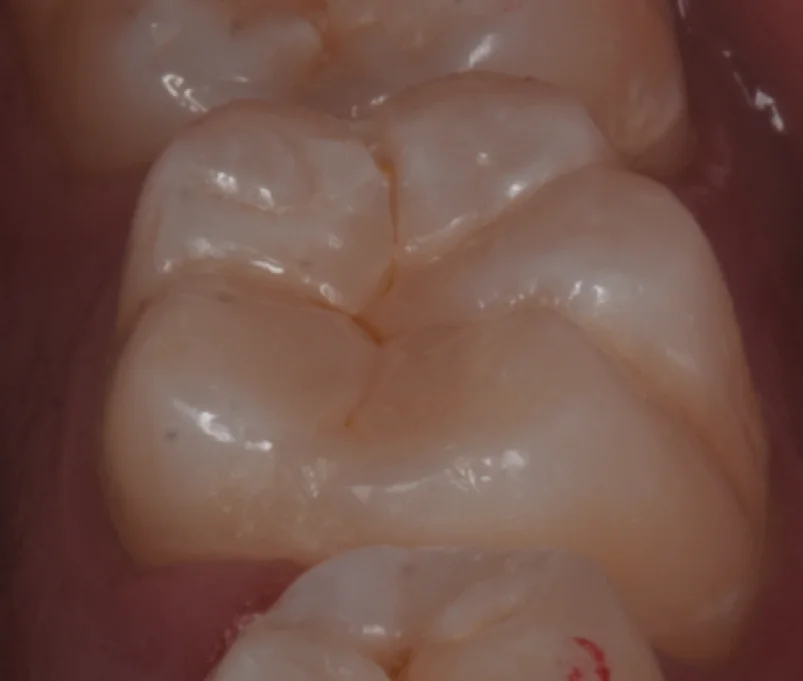

そして充填後の写真がこちらです。

溝の部分の色も手前の歯に調和させるようにしたので、違和感もあまりなく詰められたかと思います。

斜めからの写真がこちら。

ちょっとレンズに汚れがついていたのか黒い点が写ってしまっていますね(⌒-⌒; )

ちなみに術前術後の写真がこちらになります。

随分違和感なく仕上げられたとは思います。

本人も非常に喜んでいただけました。